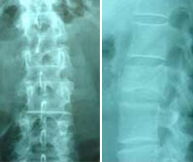

Female, Age: 55 years, Fracture L2 right. |